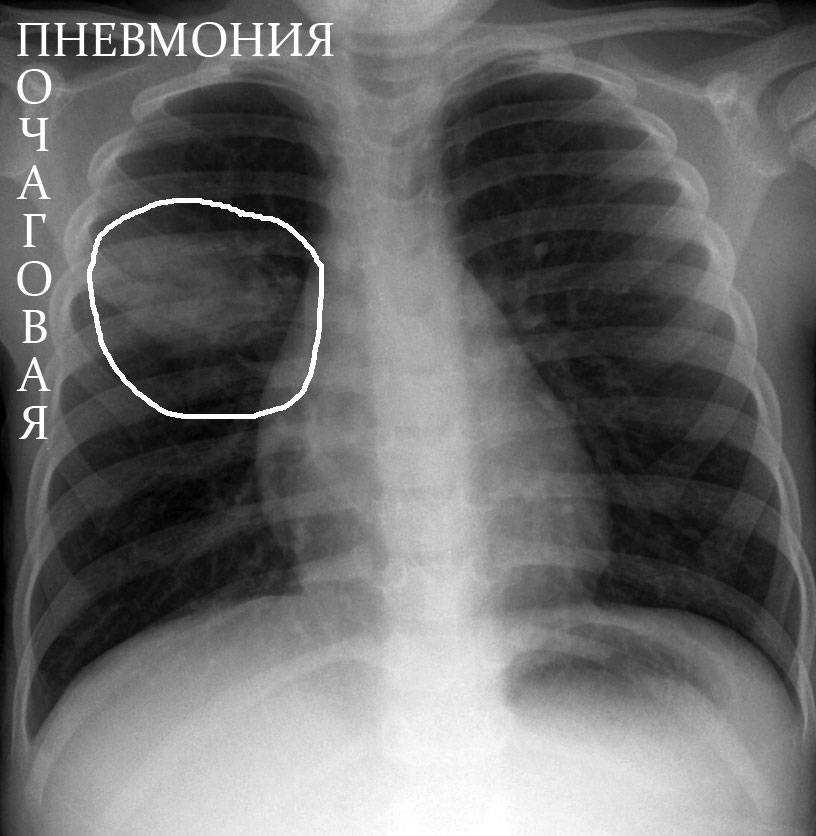

Медицинская тема: легочные осложнения при пневмонии